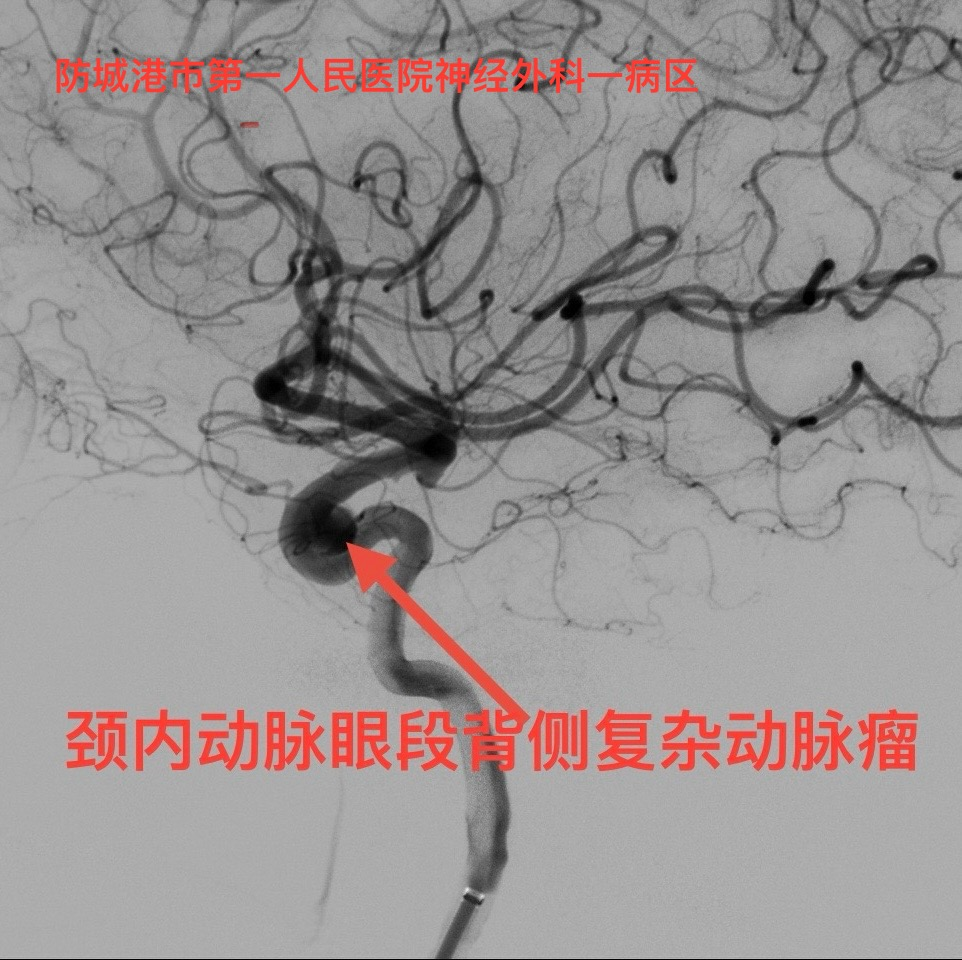

该患者为老年女性,全脑血管造影检查确诊为“左侧颈内动脉眼段背侧宽颈动脉瘤”,此类动脉瘤应用传统的弹簧圈栓塞技术治疗效果欠佳,治愈率低,复发率高。神经外科一区介入团队决定采用前沿的“密网支架植入术”,即利用密网支架的“血流导向效应”促进动脉瘤血栓化以及载瘤动脉内膜修复渐愈合。神经外科一区介入团队凭借丰富的手术经验,术中默契配合,1小时完成手术治疗,成功将颅内血流导向装置植入预定位置,术后患者恢复良好,无神经功能损伤。

患者影像资料